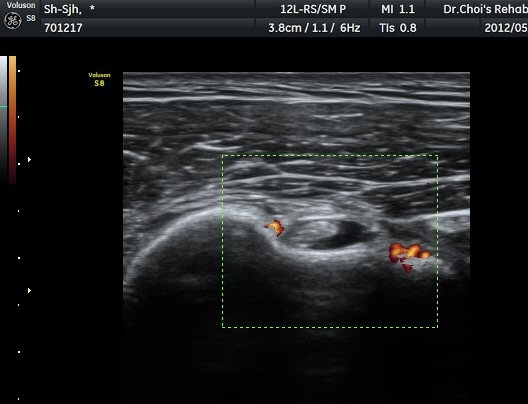

Á߸³»óÅ ¾î±ú ¾Õ Ⱦ´Ü¸é°Ë»ç¿¡¼­ À̺ειڱ٠ÁÖÀ§¿¡ ¼ö¾×Àú·ù°¡ °üÂûµÇ°í(»çÁø 1) ÆÄ¿öµµÇ÷¯

°Ë»ç¿¡¼­ Ç÷·ùÁõ°¡°¡ °üÂûµÈ´Ù(»çÁø 2). À̵ιڱ٠Á¾´Ü¸é°Ë»ç¿¡¼­µµ °Ç ÁÖÀ§ ¼ö¾×Àú·ù°¡ È®ÀÎ